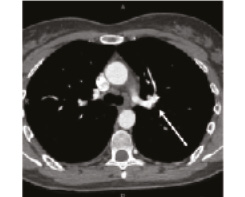

В 1993 г. на основании характерных признаков электрокардиограммы (ЭКГ) при профилактическом обследовании диагностирован феномен Вольфа–Паркинсона–Уайта. Клинических проявлений, снижающих качество жизни, пациентка не отмечала. К врачам далее не обращалась. В связи с появлением в 2015 г. одышки, перебоев в работе сердца, сердцебиения наблюдалась у участкового терапевта с диагнозом: ишемическая болезнь сердца, гипертоническая болезнь. Эхокардиография (ЭхоКГ), нагрузочные тесты не проводились. На фоне приема лозартана 25 мг/сут достигнуты целевые значения АД. В январе 2017 г. в связи с зарегистрированным на ЭКГ пароксизмом тахикардии с узкими комплексами QRS пациентка в порядке скорой помощи поступила с диагнозом «пароксизмальная суправентрикулярная тахикардия» в ЦРБ, где ритм был медикаментозно восстановлен. Далее в краевой больнице проведено внутрисердечное электрофизиологическое исследование и по его результатам – радиочастотная аблация дополнительных проводящих путей. Послеоперационный период протекал без осложнений. Однако в июне 2017 г. вновь появилась одышка при выполнении привычного объема физической нагрузки. По данным ЭКГ и рентгенограммы органов грудной клетки патологии не выявлено. Вскоре появилось кровохарканье (в течение 3 дней), и пациентка была направлена к фтизиатру, которым исключен туберкулез легких. 27.07.2017 на фоне значительного усиления одышки, выраженной тахикардии она потеряла сознание и в порядке скорой помощи доставлена в дежурный стационар, где травматологом и неврологом исключены сотрясение головного мозга и закрытая черепно-мозговая травма. Пациентка отпущена домой. В связи с сохраняющейся одышкой при подъеме на один лестничный пролет в августе 2017 г. по собственной инициативе она обратилась к кардиологу. При проведении ЭхоКГ выявлены увеличение правых камер сердца и признаки их объемной перегрузки. С предварительным диагнозом ТЭЛА пациентка направлена в дежурный стационар, где в экстренном порядке проведена спиральная компьютерная томография (СКТ) с контрастированием легочной артерии. Выявлены признаки легочной тромбоэмболии крупных и средних ветвей легочной артерии (ЛА) с обеих сторон (рис. 1–4). При целенаправленном сборе анамнеза выяснилось, что в течение 3 лет (с 2014 г.) пациентка принимает Линдинет 20 мг – монофазный пероральный контрацептив (этинилэстрадиол + гестоден), назначенный гинекологом с целью контрацепции. По данным ультразвукового исследования вен нижних конечностей выявлен тромбоз суральных вен справа. Линдинет отменен. На фоне лечения антикоагулянтами (гепарин, эноксапарин) состояние женщины несколько улучшилось. Она переведена на варфарин, который далее заменен на апиксабан в дозе 10 мг 2 раза в день.

СКТ с контрастированием ЛА | |

14.08.2018 | 26.09.2018 |

Рис. 3: а – тромбы в нижнедолевой ветви левой ЛА и нижнедолевой ветви правой ЛА; б – сохраняется тромбоз нижнедолевой ветви правой ЛА. | |

Рис. 4: а – тромбы в левой ЛА и ее ветвях; б – тромбоза левой ЛА (нисходящей ветви) не выявлено, сохраняется тромбоз нижнедолевой ветви левой ЛА. | |

По данным чресприщеводной ЭхоКГ тромбоза камер сердца не обнаружено, однако уровень D-димера – более 250 мкг/л. Исследования в отношении патологии гемостаза выявили значительный дефицит протеинов С и S. Проведена замена апиксабана на ривароксабан 15 мг 2 раза в сутки с последующим переводом на прием ривароксабана 20 мг 1 раз в сутки в связи с большей биодоступностью последнего. Также с целью усиления антитромботического эффекта к терапии добавлен клопидогрел в дозе 75 мг в сутки. При проведении СКТ органов грудной клетки с контрастированием легочной артерии 26.09.2018 выявлена положительная динамика (см. рис. 1, б, рис. 4). Состояние стабилизировалось, рецидивы одышки прекратились. От имплантации кава-фильтра пациентка отказалась.